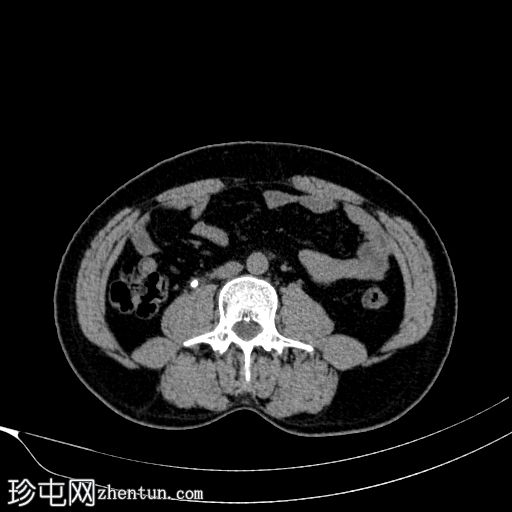

CT

轴位

平扫

右侧输尿管中段可见一卵圆形不透光结石,最大直径约6 mm,平均CT值约830 HU。该结石伴右侧近端输尿管及肾盂肾盏系统轻度扩张。

左侧输尿管轻度积水,未见明显梗阻性结石。

本病例展示了输尿管结石梗阻的典型CT表现,即上游反压改变。

未见肾周脂肪浸润、穹窿部破裂或尿瘤。